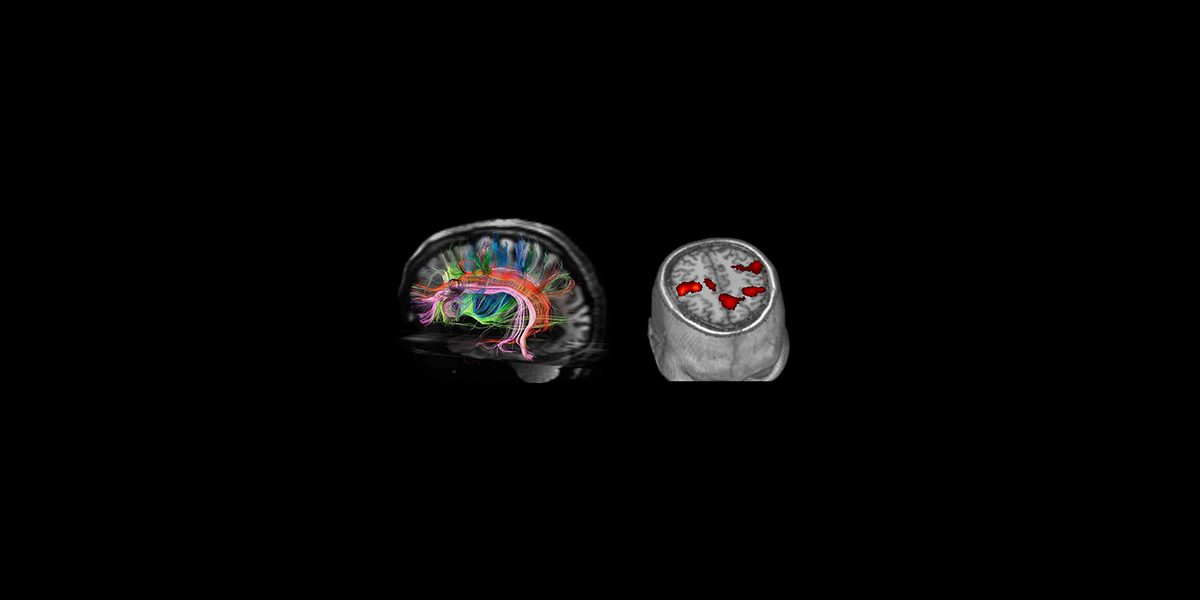

QBase will provide consultation services (Data analysis and modelling) using state of the art neuroimaging data (fMRI, DTI, 3D Volumetrics) and methods (GLM, DCM, TBSS, Graph theory, DARTEL, Surface analysis) as well as robotic device outputs, serious game score elements and clinical data. Prognostic models will be constructed using standard statistical tools (i.e. Generalized equation modelling) and machine learning approaches.

Stroke is a major cause of morbidity and invalidity in modern society. A novel Magnetic Resonance Compatible Hand Robotic Device combined with state-of-the-art in vivo magnetic resonance imaging of brain structure and function will provide biomarkers that can be used to evaluate and predict the effects of training on the motor skills and brain recovery of stroke patients. The findings will advance stroke recovery research, which has been hampered from the longstanding view that lost functions were not recoverable and may ultimately contribute to improving the quality of life of stroke patients especially in the elderly where stroke is more prevalent.